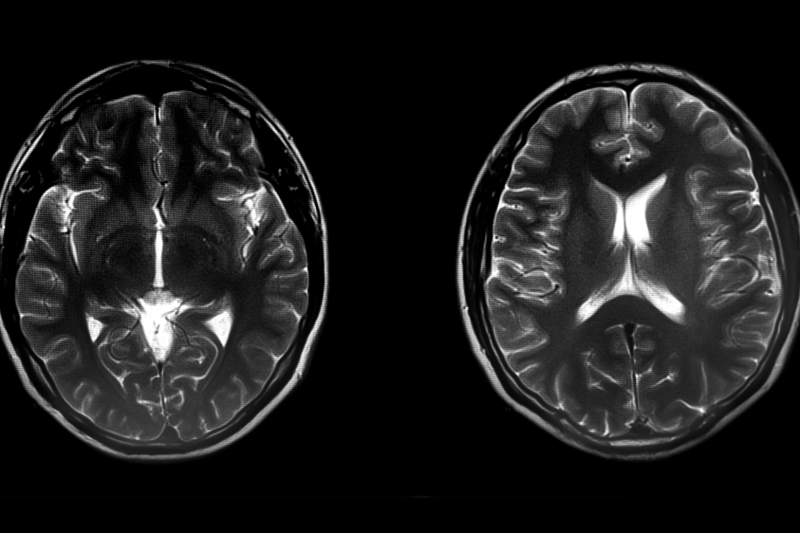

“The more amyloid or tau you have in the brain, the sicker the brain becomes,” said Dr. Cyrus Raji, associate professor of radiology at Washington University School of Medicine. “We track a sicker-looking brain by measuring lower blood flow and brain atrophy in the hippocampus, a key part of the memory center.”Obesity has become a global epidemic. The World Health Organization predicts that within the next decade, over half of the world’s population will be overweight or obese. In the United States alone, nearly 260 million people are projected to fall into this category by 2050 without significant policy interventions.

“Visceral fat is metabolically abnormal and diabetes-inducing,” Raji explained. “It receives more blood flow, is more hormonally active, and significantly contributes to inflammation and brain atrophy.”